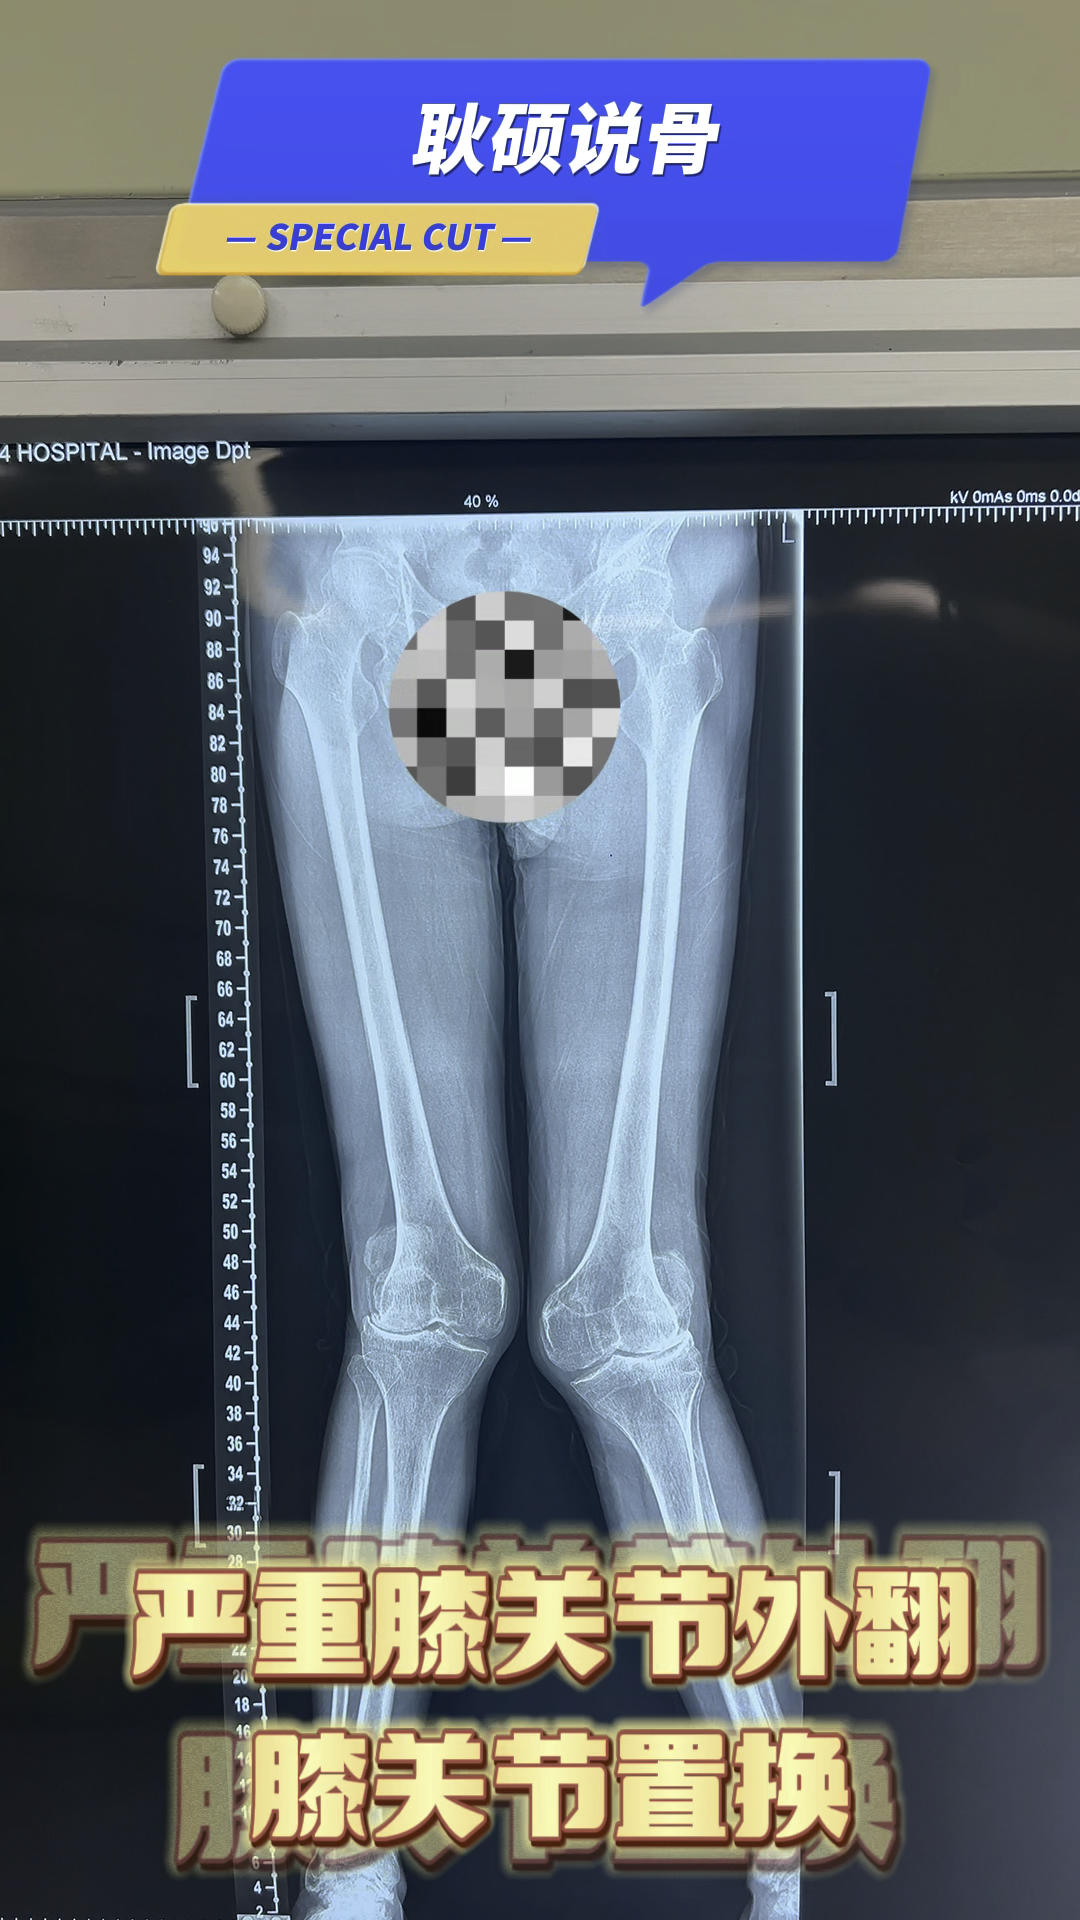

严重外翻膝关节畸形,走路困难,行走困难,膝关节置换

图片尺寸1080x1920